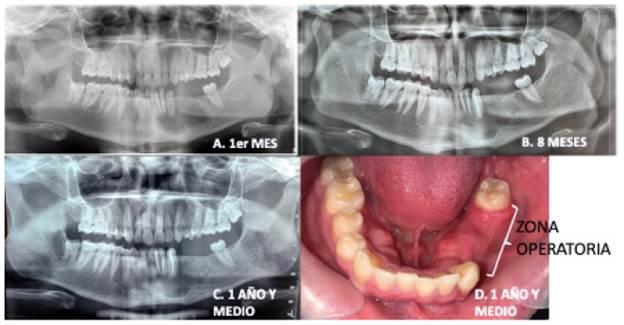

El seguimiento se llevó a cabo al mes del procedimiento con una radiografía panorámica, en la que se observó una disminución de la zona radiolúcida, en comparación con la situación inicial. En dicho mes se habían dado indicaciones de lavado con clorhexidina al 0.12 % más digluconato cada 12 horas durante los 30 días, a través de la sonda Nelaton, que conecta con la luz quística. En este control, se remitió el paciente al endodoncista, para el tratamiento del órgano dentario 33. Posteriormente, hubo controles a los 8 meses y al año y medio, tanto imagenológicamente como clínicamente, donde se puede ver la regeneración ósea casi completa (figura 4).

Figura 4 Seguimiento. A) A un mes. B) A los 8 meses. C) Al año y medio. D) Regeneración ósea al año y medio

Por la evolución que ha presentado el paciente, sin sintomatologia ni recidiva de la lesión después de 23 meses de control y sin necesidad de haber usado la sc, dentro del plan de tratamiento se plantea extraerle los terceros molares y regenerar la zona con injerto en bloque y particulado para colocarle implantes en la zona posteroinferior izquierda, seguido de rehabilitación sobre estos. No obstante, por falta de sustento económico, no puede iniciar dicho tratamiento y se maneja con prótesis removible. Por todo ello, se puede decir que al día de hoy el paciente presenta una buena evolución; sin embargo, se sugiere darle al caso un seguimiento durante más de cinco años.